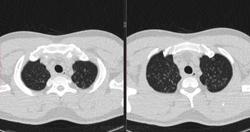

По jpeg впечатление очаговых изменений верхних долей и умеренного увеличения лимфоузлов средостения. Туберкулез на первое место.

Моё мнение то же самое, туберкулез. Добавила изображения.

Посев мокроты на туберкулез отрицательный. Пульмонолог по КТ ставит саркоидоз легких 2 степени. Какое Ваше мнение?

В диф. ряд на первое место предполагаю все же саркоидоз легких и ВГЛУ (по одной из классификаций 2 стадия, а не степень). В плане дальнейшего диагностического алгоритма: